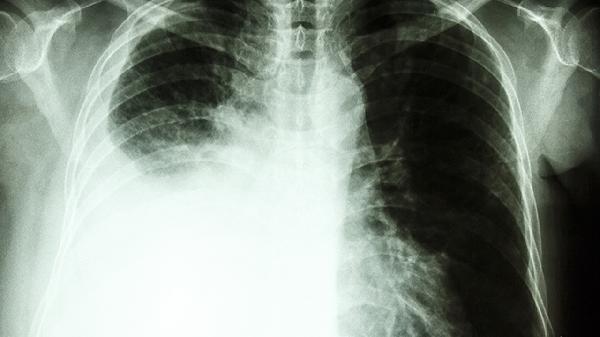

急性肺组织胞浆菌病多见于健康人群吸入大量孢子后发病,通常表现为自限性呼吸道感染。患者可能出现发热、咳嗽、胸痛、乏力等流感样症状,胸部影像学可见肺部结节或纵隔淋巴结肿大。多数患者无须特殊治疗,症状可在数周内自行缓解。重症患者可遵医嘱使用伊曲康唑胶囊或两性霉素B脂质体进行抗真菌治疗。

慢性肺组织胞浆菌病好发于有基础肺疾病的中老年人群,病程常超过3个月。典型表现为咳嗽咳痰、低热、盗汗及进行性呼吸困难,影像学可见肺尖纤维空洞性病变,易与肺结核混淆。治疗需长期使用抗真菌药物如伏立康唑片或泊沙康唑口服混悬液,疗程通常需要6-12个月。合并肺气肿等基础疾病者需同时进行呼吸功能康复训练。